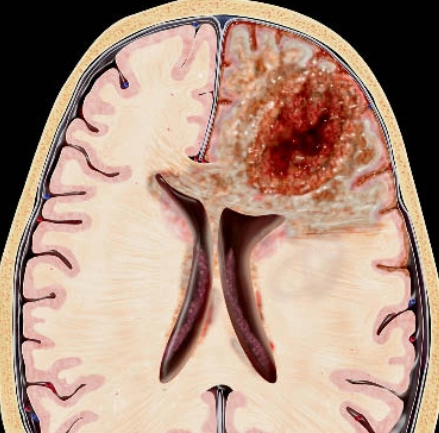

U nguyên bào thần kinh đệm (Glioblastoma- GBM)